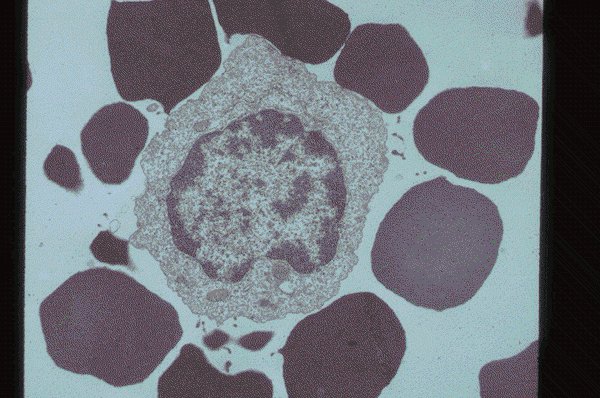

Set 1 Normal and Abnormal Peripheral Blood Cells

Slide 12 of 200 Image ID 2962

Sheep red cell rosette surrounding a T-cell

A sheep red cell rosette has formed around a T

lymphocyte in this electron photomicrograph.